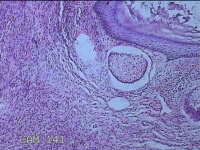

双侧肩锁关节处肿物

性别

女

年龄

30岁

临床诊断

纤维瘤病

一般病史

无

标本名称

大体所见

灰白暗红色肿物2x1.3x0.8cm两个,表面糜烂,切开肿物呈实性,切面灰白粉红色,质软。